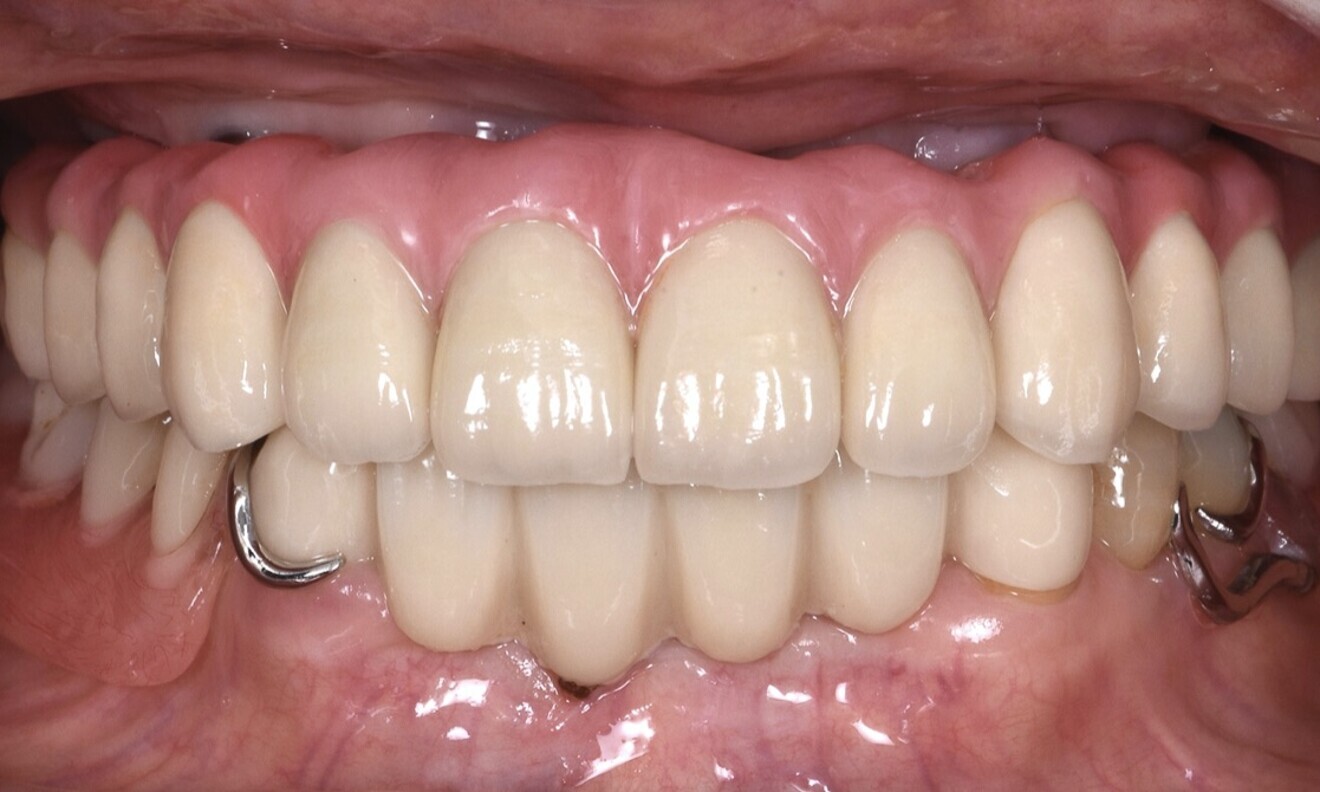

After two years, clinical and radiographic control of the rehabilitation was carried out (Figs. 14 & 15). The soft and hard tissue surrounding the implant exhibited favourable conditions. Furthermore, the patient had gained a deeper understanding of her oral health and acquired knowledge on how to maintain proper oral care.